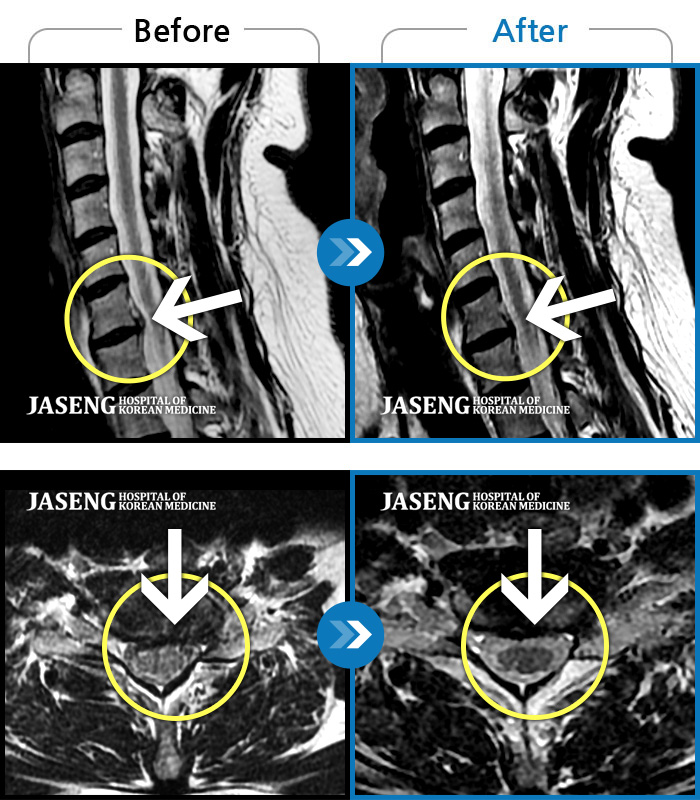

목통증, 왼쪽 팔저림, 두통, 잇몸통증까지 심해 일상생활 불가